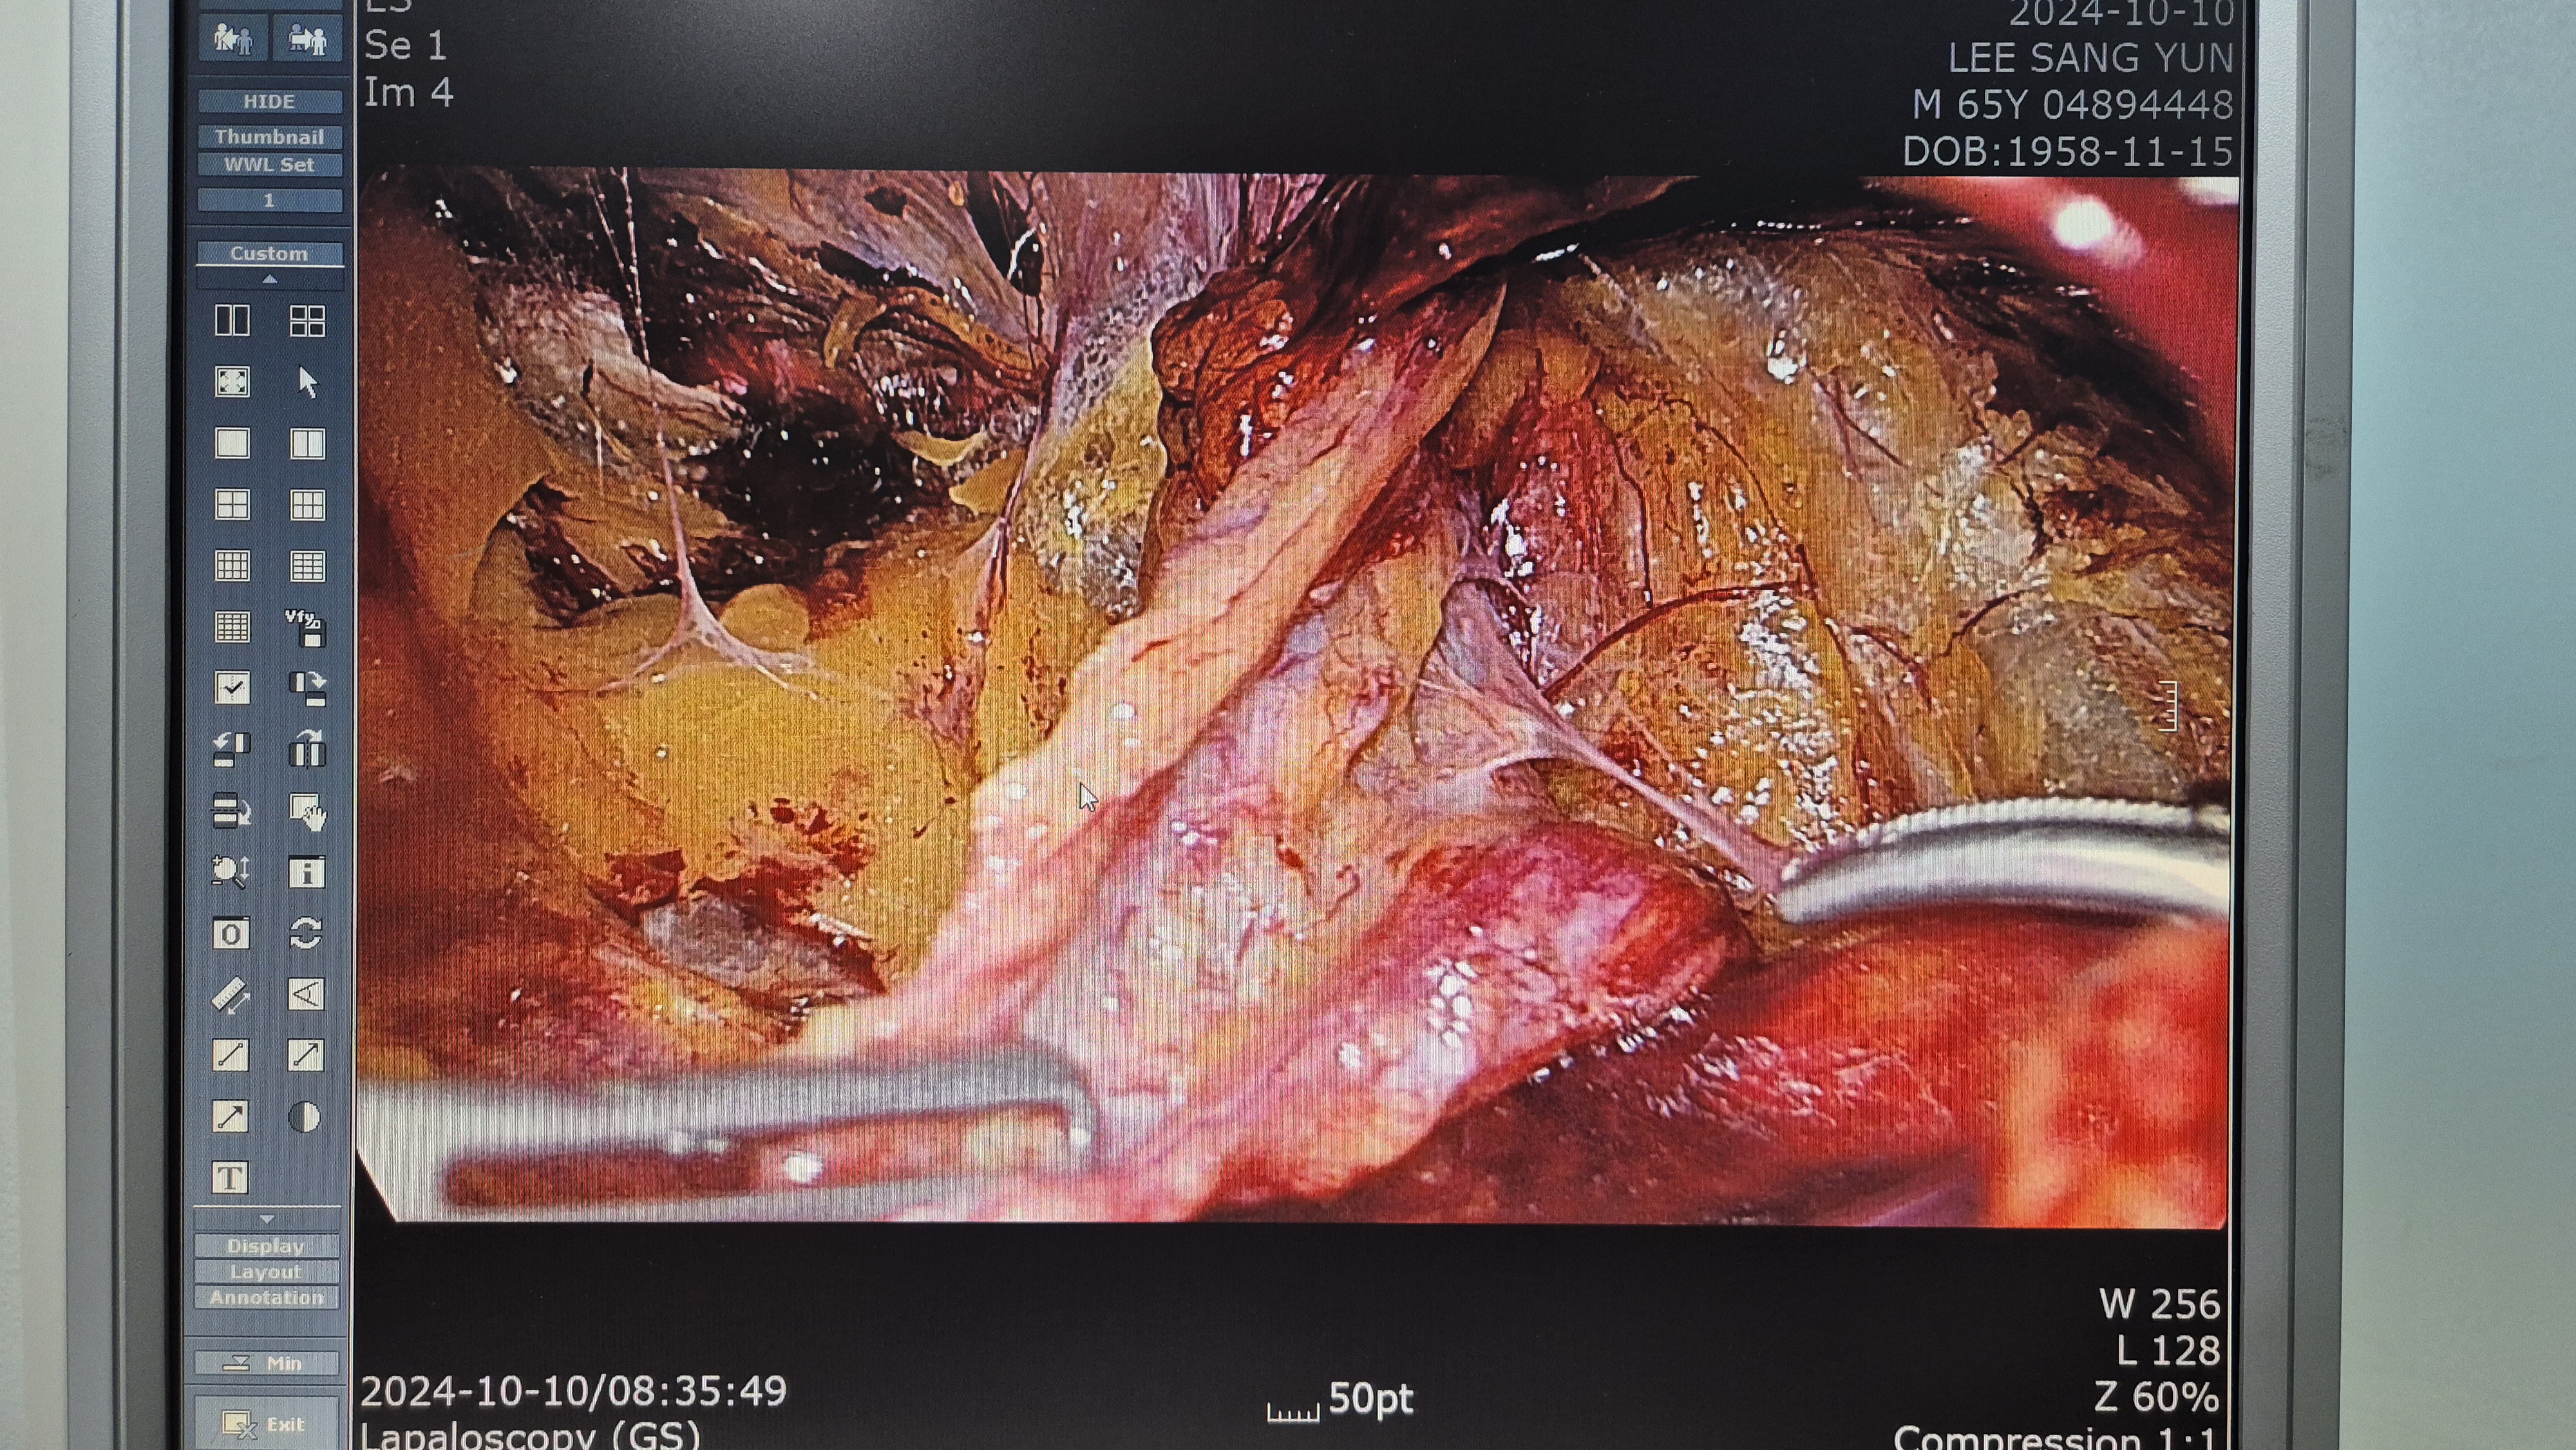

포항성모병원 외과 서수한입니다.

우측 서혜부 종물 주소로 내원하여 초음파 시행후 서혜부 탈장으로 확인되어,

방금 복강경 탈장교정술을 시행했습니다.

수술은 15분 걸렸습니다.